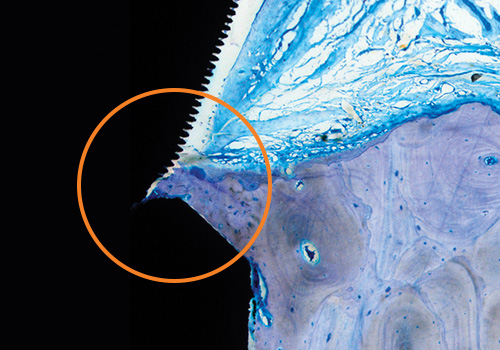

Laser-Lok microchannels is a proprietary dental implant surface treatment developed from over 30 years of research initiated to create the optimal implant surface. Through this research, the unique Laser-Lok surface has been shown to elicit a biologic response that includes the inhibition of epithelial downgrowth and the attachment of connective tissue.1,2 This physical attachment produces a biologic seal around the implant that protects and maintains crestal bone health. The Laser-Lok phenomenon has been shown in post-market studies to be more effective than other implant designs in reducing bone loss.3,4,5,6

1. Human Histologic Evidence of a Connective Tissue Attachment to a Dental Implant. M Nevins, ML Nevins, M Camelo, JL Boyesen, DM Kim. International Journal of Periodontics & Restorative Dentistry. Vol. 28, No. 2, 2008.